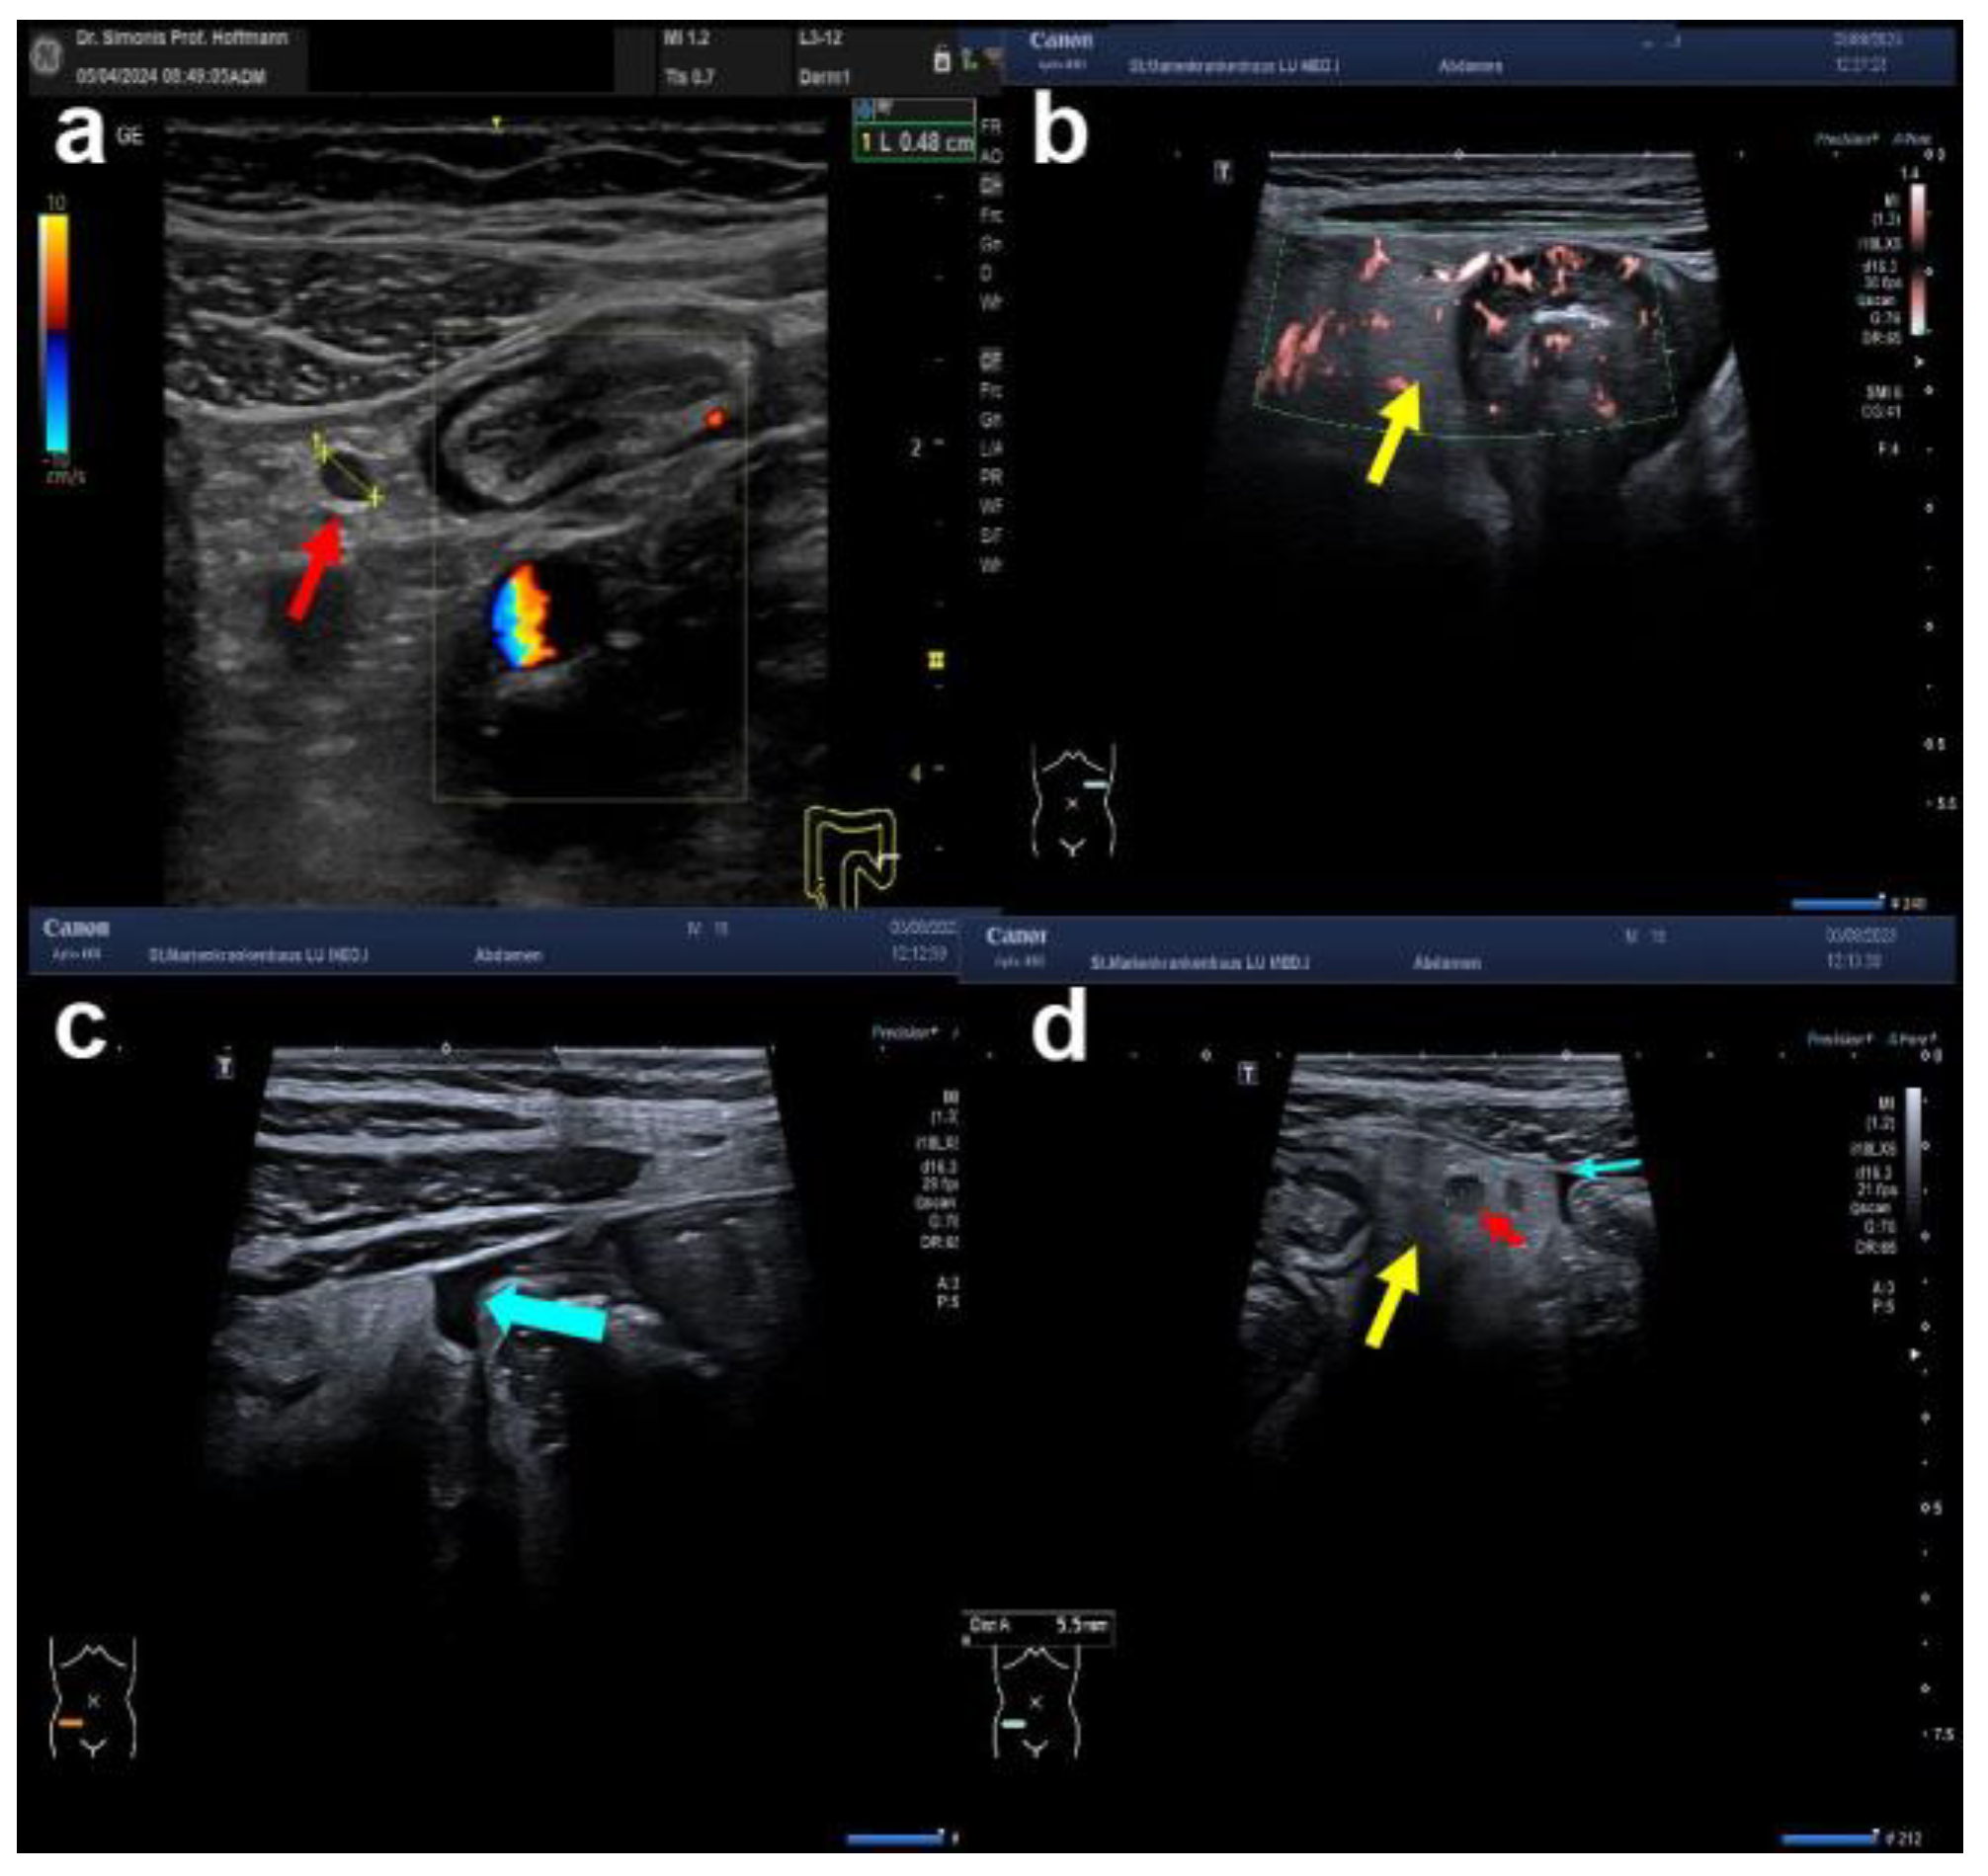

6. IUS-Based Detection of Fistulae, Inflammatory Masses, and Abscesses in Patients with Crohn’s Disease

- Maconi, G.; Sampietro, G.M.; Russo, A.; Bollani, S.; Cristaldi, M.; Parente, F.; Dottorini, F.; Bianchi Porro, G. The Vascularity of Internal Fistulae in Crohn’s Disease: An in Vivo Power Doppler Ultrasonography Assessment. Gut 2002, 50, 496–500. [Google Scholar] [CrossRef] [PubMed]

- Pruijt, M.J.; de Voogd, F.A.E.; Montazeri, N.S.M.; van Etten-Jamaludin, F.S.; D’Haens, G.R.; Gecse, K.B. Diagnostic Accuracy of Intestinal Ultrasound in the Detection of Intra-Abdominal Complications in Crohn’s Disease: A Systematic Review and Meta-Analysis. J. Crohns Colitis 2024, 18, 958–972. [Google Scholar] [CrossRef] [PubMed]

| abscess (hypoechoic area, no CDS) | [present; absent] | ||

| fistula (hypoechoic tract) | [present; absent] | ||